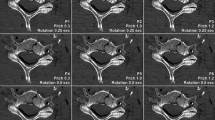

The lowest image noise overall was recorded for full-dose non-UHR-PCD-CT (40.3 ± 7.2 HU), corresponding to the highest SNR among all scan protocols (4.2 ± 1.5). In contrast, the highest image noise was measured in low-dose EID-CT (97.7 ± 18.0 HU), corresponding with the lowest SNR (1.8 ± 0.7). Side-by-side analysis of axial reformations of EID-CT and PCD-CT data used for ROI-based measurements is provided in Fig. 3. Comparing the individual PCD-CT datasets, image noise was lowest and SNR were highest in non-UHR reconstructions at either dose level. Notably, no difference was found between full-dose UHR (noise: 48.9 ± 7.5 HU; SNR: 3.5 ± 1.2) and low-dose non-UHR-PCD-CT (48.4 ± 7.7 HU; 3.5 ± 1.3) for both objective criteria assessed within this study (both p > 0.99). Nevertheless, UHR-PCD-CT reconstructions at either dose level were associated with considerably less image noise than the dose-equivalent EID-CT datasets. Even between full-dose EID-CT (noise: 78.2 ± 6.4 HU; SNR: 2.2 ± 0.9) and low-dose UHR-PCD-CT (48.4 ± 7.7 HU; 3.5 ± 1.3), superior results regarding the latter were ascertained (both p < 0.001). Quantitative criteria of image quality for each scan and reconstruction are summarized in Table 3.

Representative axial CT slices at the level of the acromioclavicular joint demonstrate the image quality with all six combinations of dose protocol and detector technology. Increased image noise with lower dose in EID-CT limits assessability of cancellous bone structures. Upper row: Full-dose scan protocols (10.0 mGy): EID-CT, non-UHR-PCD-CT, UHR-PCD-CT. Lower row: Low-dose scan protocols (5.0 mGy): EID-CT, non-UHR-PCD-CT, UHR-PCD-CT.